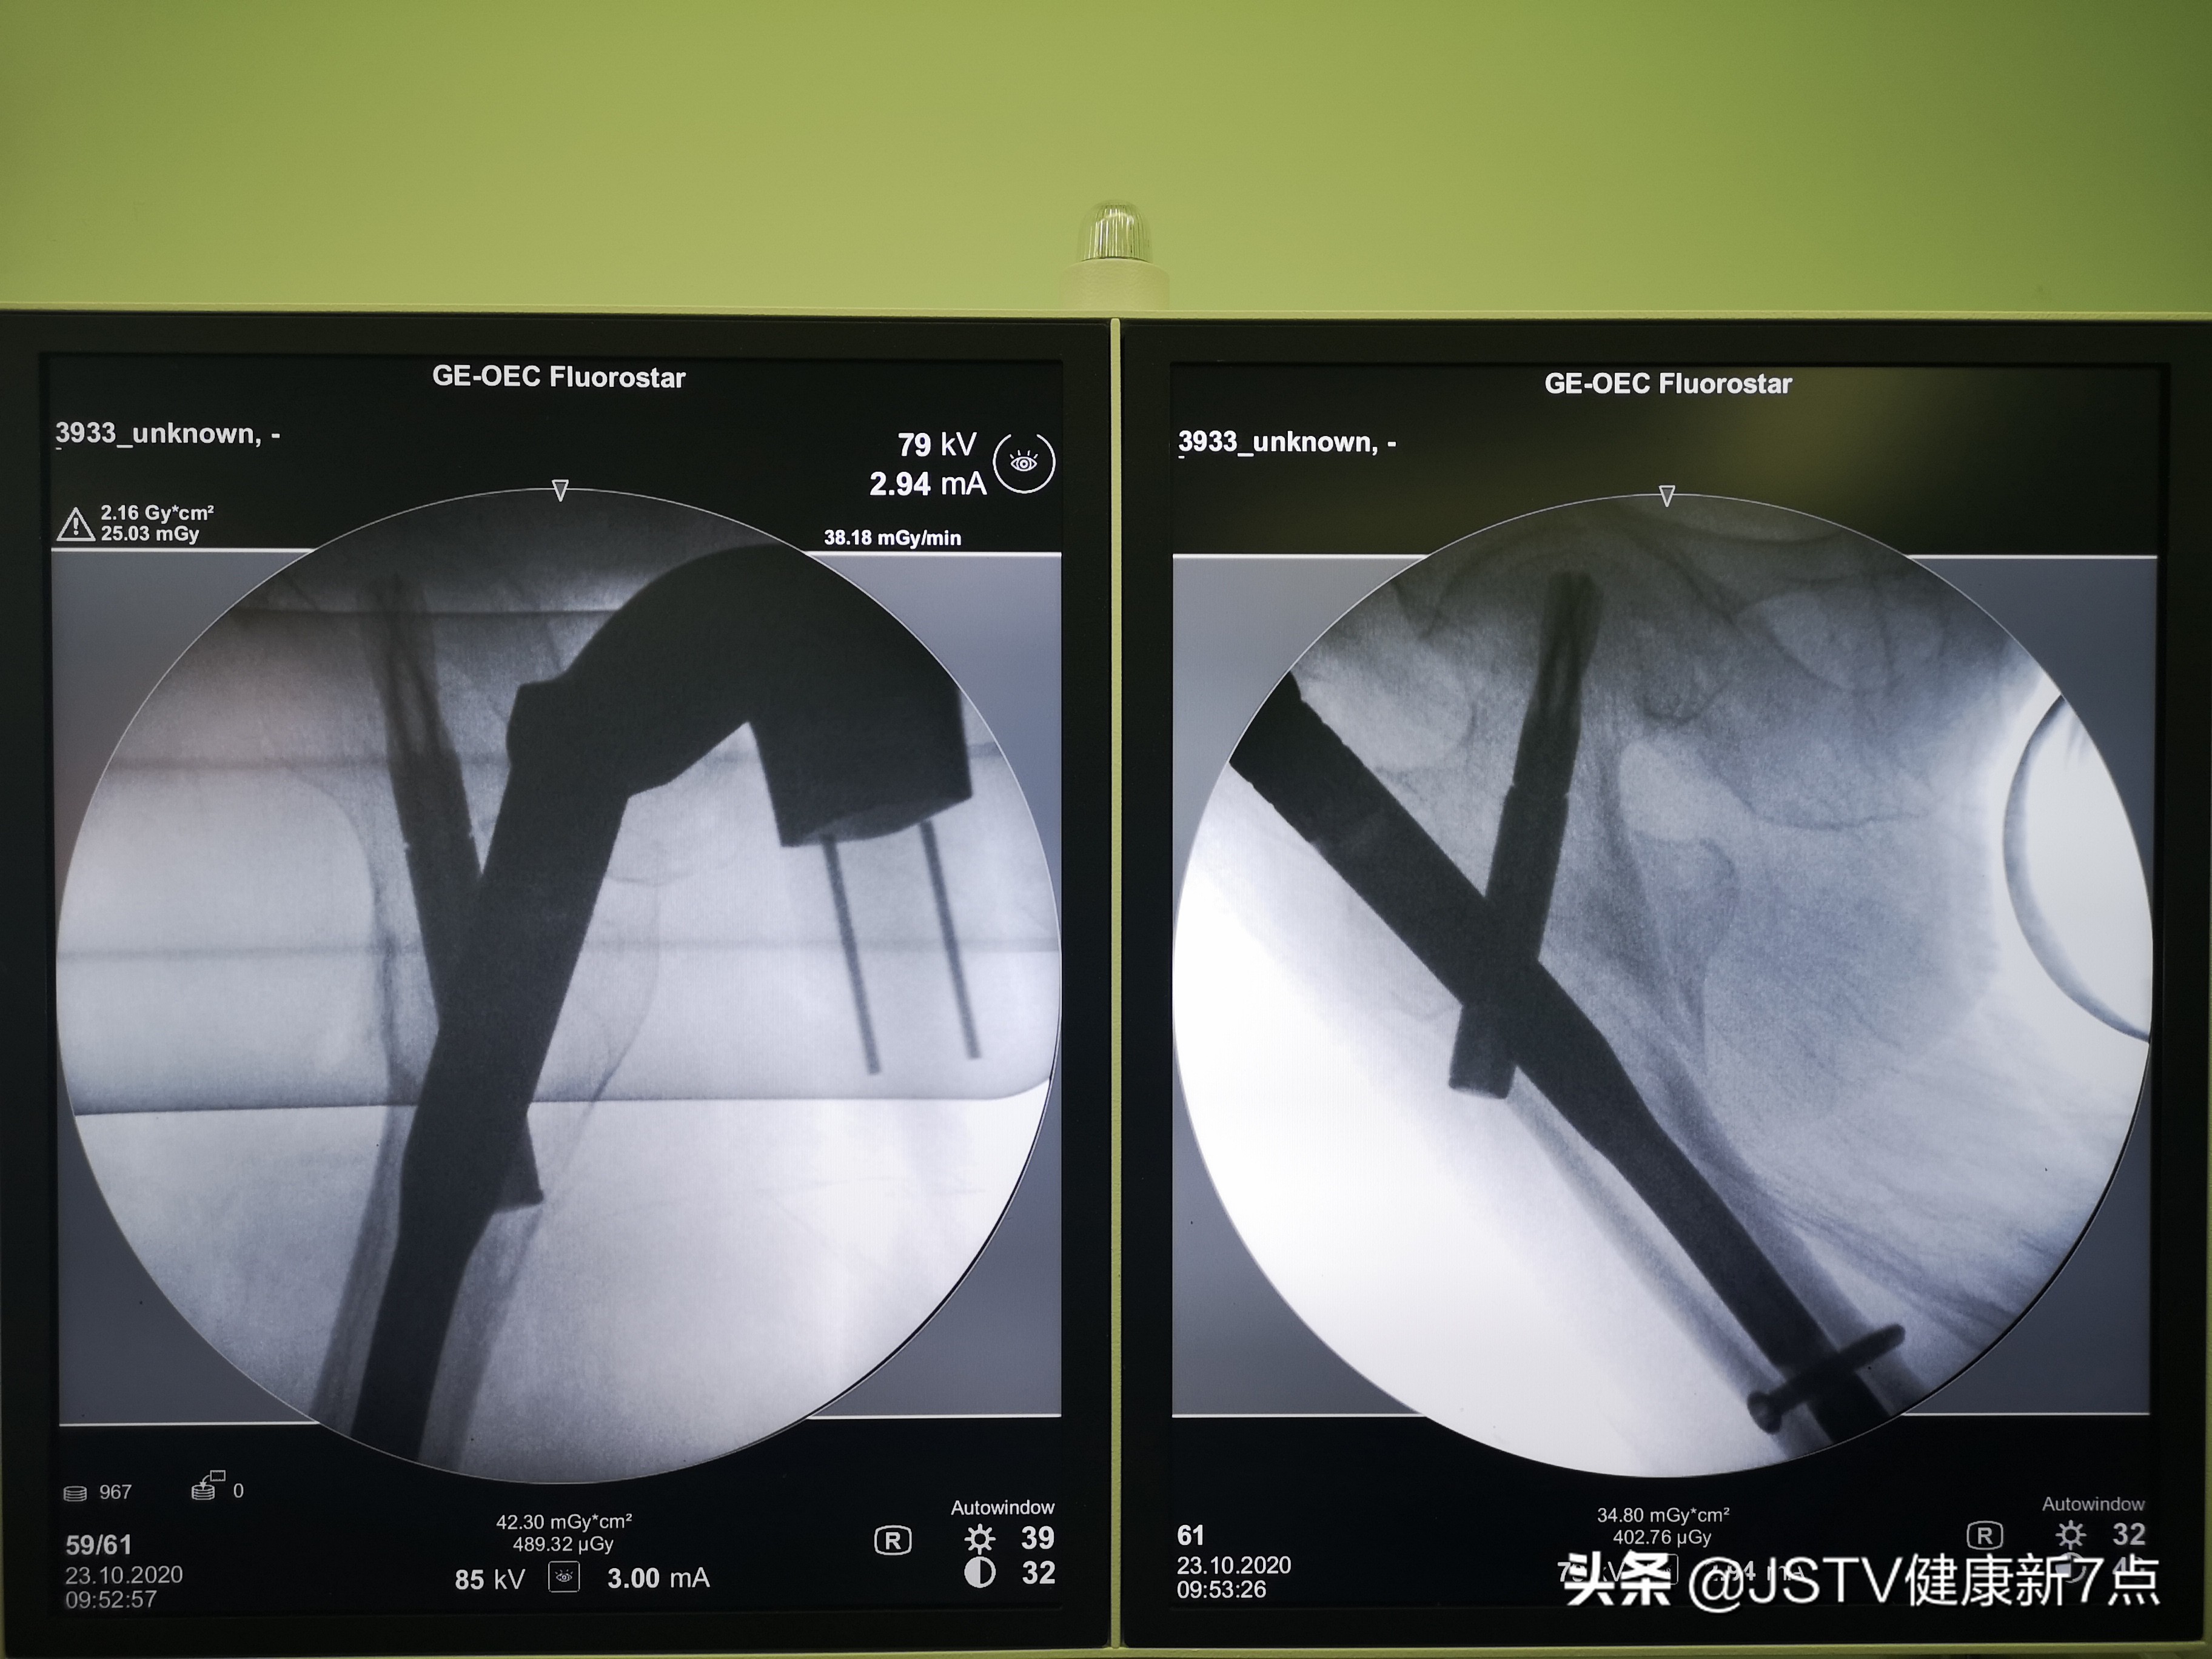

一番探讨后,梁斌主任团队决定为93岁高龄的李奶奶实施右股骨粗隆间骨折闭合复位微创内固定术。该手术的优点在于,医生先通过牵引床在x射线下复位,在复位满意后进行微创内固定操作,手术一般在大腿外侧取三个切口,长度基本在2公分左右,通过髓内钉固定分离的骨折块,全程操作在x线引导下进行,微创手术出血少,患者损伤小,恢复快。

梁斌主任团队正在C型臂X光机下进行微创手术

修复瓷器只需要将每一个瓷片拼接起来,但是骨科手术不一样,病患的骨折处没有显露在外,在切口小,在看不到骨折的具体情况下如何去接骨头呢?所以,骨科医生只能在cbx光机的引导下进行手术操作。从手术的定位,骨折的复位以及按标准流程一步步的将钉植入体内,都是非常精准的。所以说,射线就是骨科手术医生的眼睛,这是整个手术中最大的难点。

接下来在射线引导下,无需将骨折部位切开,在射线下引导医生们每一步微创的操作,也就是所谓的介入式的骨科创伤固定的手术,形成了一个标准化的流程。